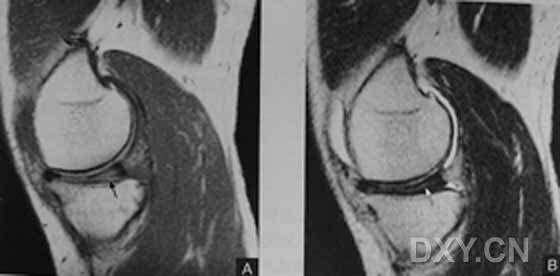

| I级 外侧半月板后角见灶性高信号,不与半月板关节面相接触

| Ⅱ级,见黑箭头